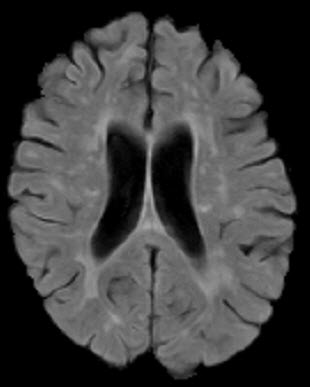

原创